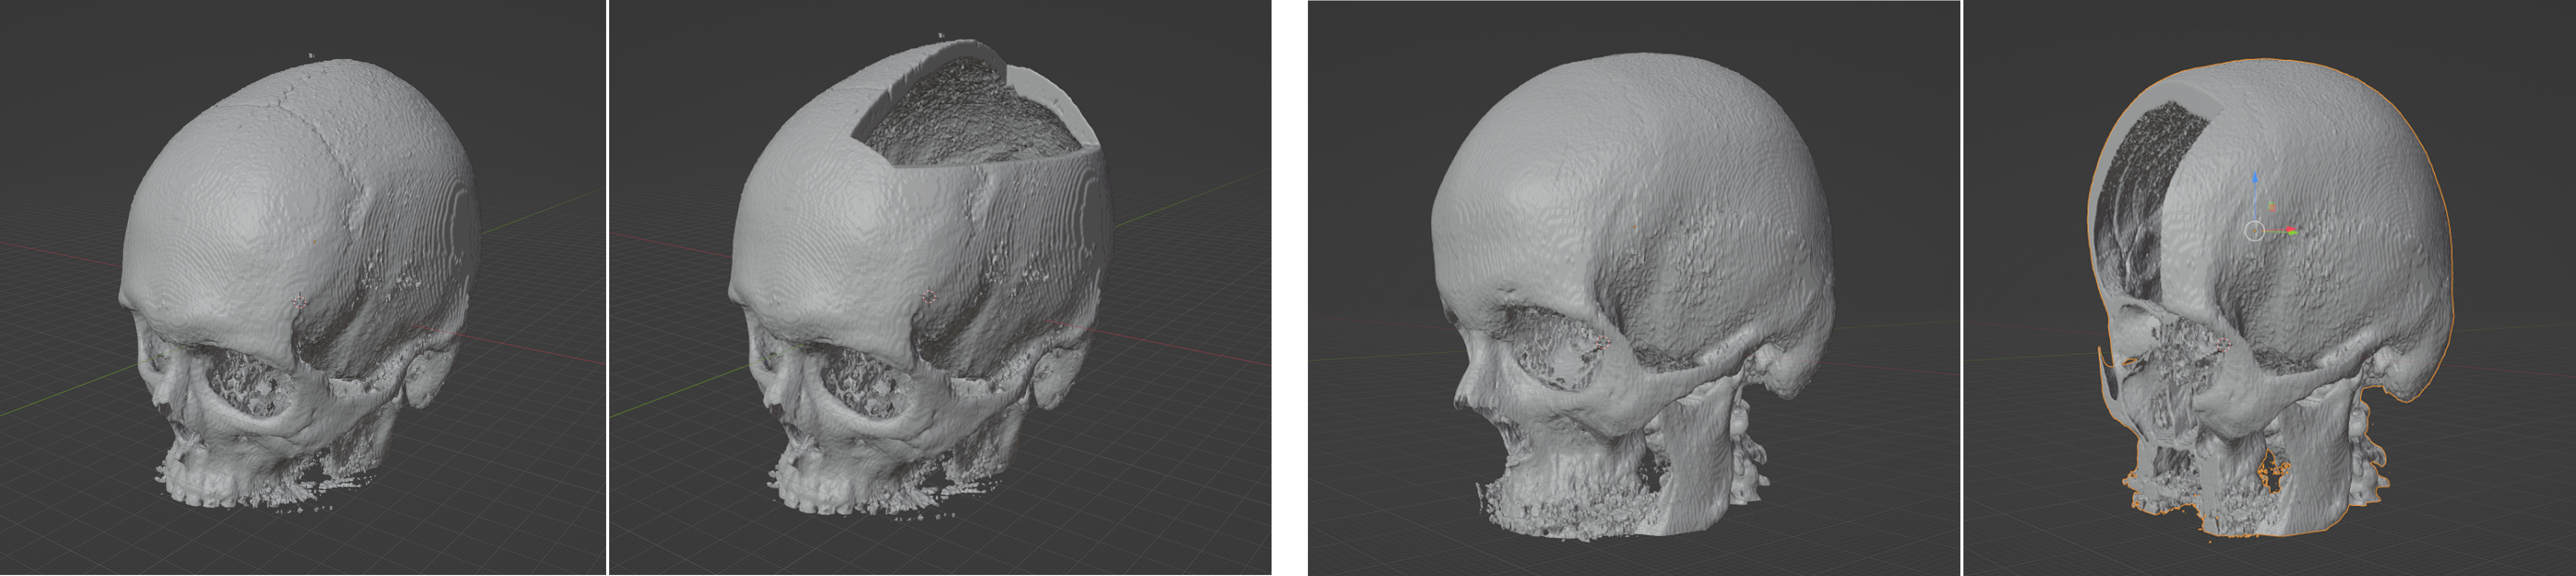

Two datasets are involved in this study. (1) the MUG500+ dataset [2], which contains 500 complete skulls (e.g., first and third column, Figure 1) in NRRD format. 21 of the image files were found to be corrupted, and were discarded. The remaining 479 complete skulls were split into a training set with 429 skulls and a test set with 50 skulls. Of the 429 complete skulls in the training set, 253 skulls are inserted with cranial defects (e.g., second column, Figure 1) and 176 skulls with facial defects (e.g., fourth column, Figure 1). Correspondingly, we created two defective cases (one with cranial defect and one with facial defect) for each of the 50 test skulls, resulting in defective test skull samples. The size, shape and position of the defects vary on different skulls. A complete-defect skull pair comprises of a defective skull (with either a cranial or a facial defect) and the corresponding complete skull. Therefore, the training set contains 429 such complete-defect pairs, and the test set contains complete-defect pairs. The cranial and facial defects were created automatically using the defect creation script in the MONAI SkullRec repository. 79 complete-defect pairs are further split from the training set for validation during training. The axial dimension of all the skull images were cropped to 256. (2) Besides the MUG500+ dataset, we also trained the MONAI network on the SkullFix dataset [3], which contains 100 complete-defect skull pairs for training and 100 pairs for evaluation. In this study, we replaced the original cranial defects with facial defects created the same way as in the MUG500+ dataset, and trained the MONAI network for automatic facial reconstruction.